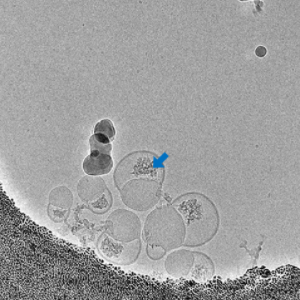

mRNA染色定位

无定形的mRNA较为松散,在电镜结果中衬度较差,难以识别,需要额外的染色操作才能定位。劳氏紫的染色原理基于其分子结构中的活性基团与细胞核中的核酸发生相互作用。劳氏紫分子中的芳香环和杂环结构使其能够与DNA和RNA中的碱基对发生π-π堆积作用,从而结合到核酸分子上。此外,劳氏紫中的氯原子和胺基可以与核酸分子中的负电荷相互作用,增强了染料与核酸的结合力。在电镜层面上看,劳氏紫的作用使mRNA密度更加致密,使电镜衬度增强。

-

染色前

染色后

LNP样品中mRNA的染色定位